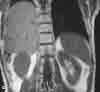

You order a CT scan to investigate these findings further.An axial image (C) demonstrates the dependent viscerasign, in which the liver makes contact with the posteriorribs (arrow); this strongly suggests a right-sided diaphragmatichernia.

You order an MRI study to confirm your suspicions.Coronal (D) and sagittal (E) T1-weighted images show arent in the center of the diaphragm (arrows) throughwhich the right lobe of the liver herniates. The CT andMRI images clearly point to increased intra-abdominal/intrapelvic pressure as the cause of both the pelvicfractures and the rupture of the diaphragm.